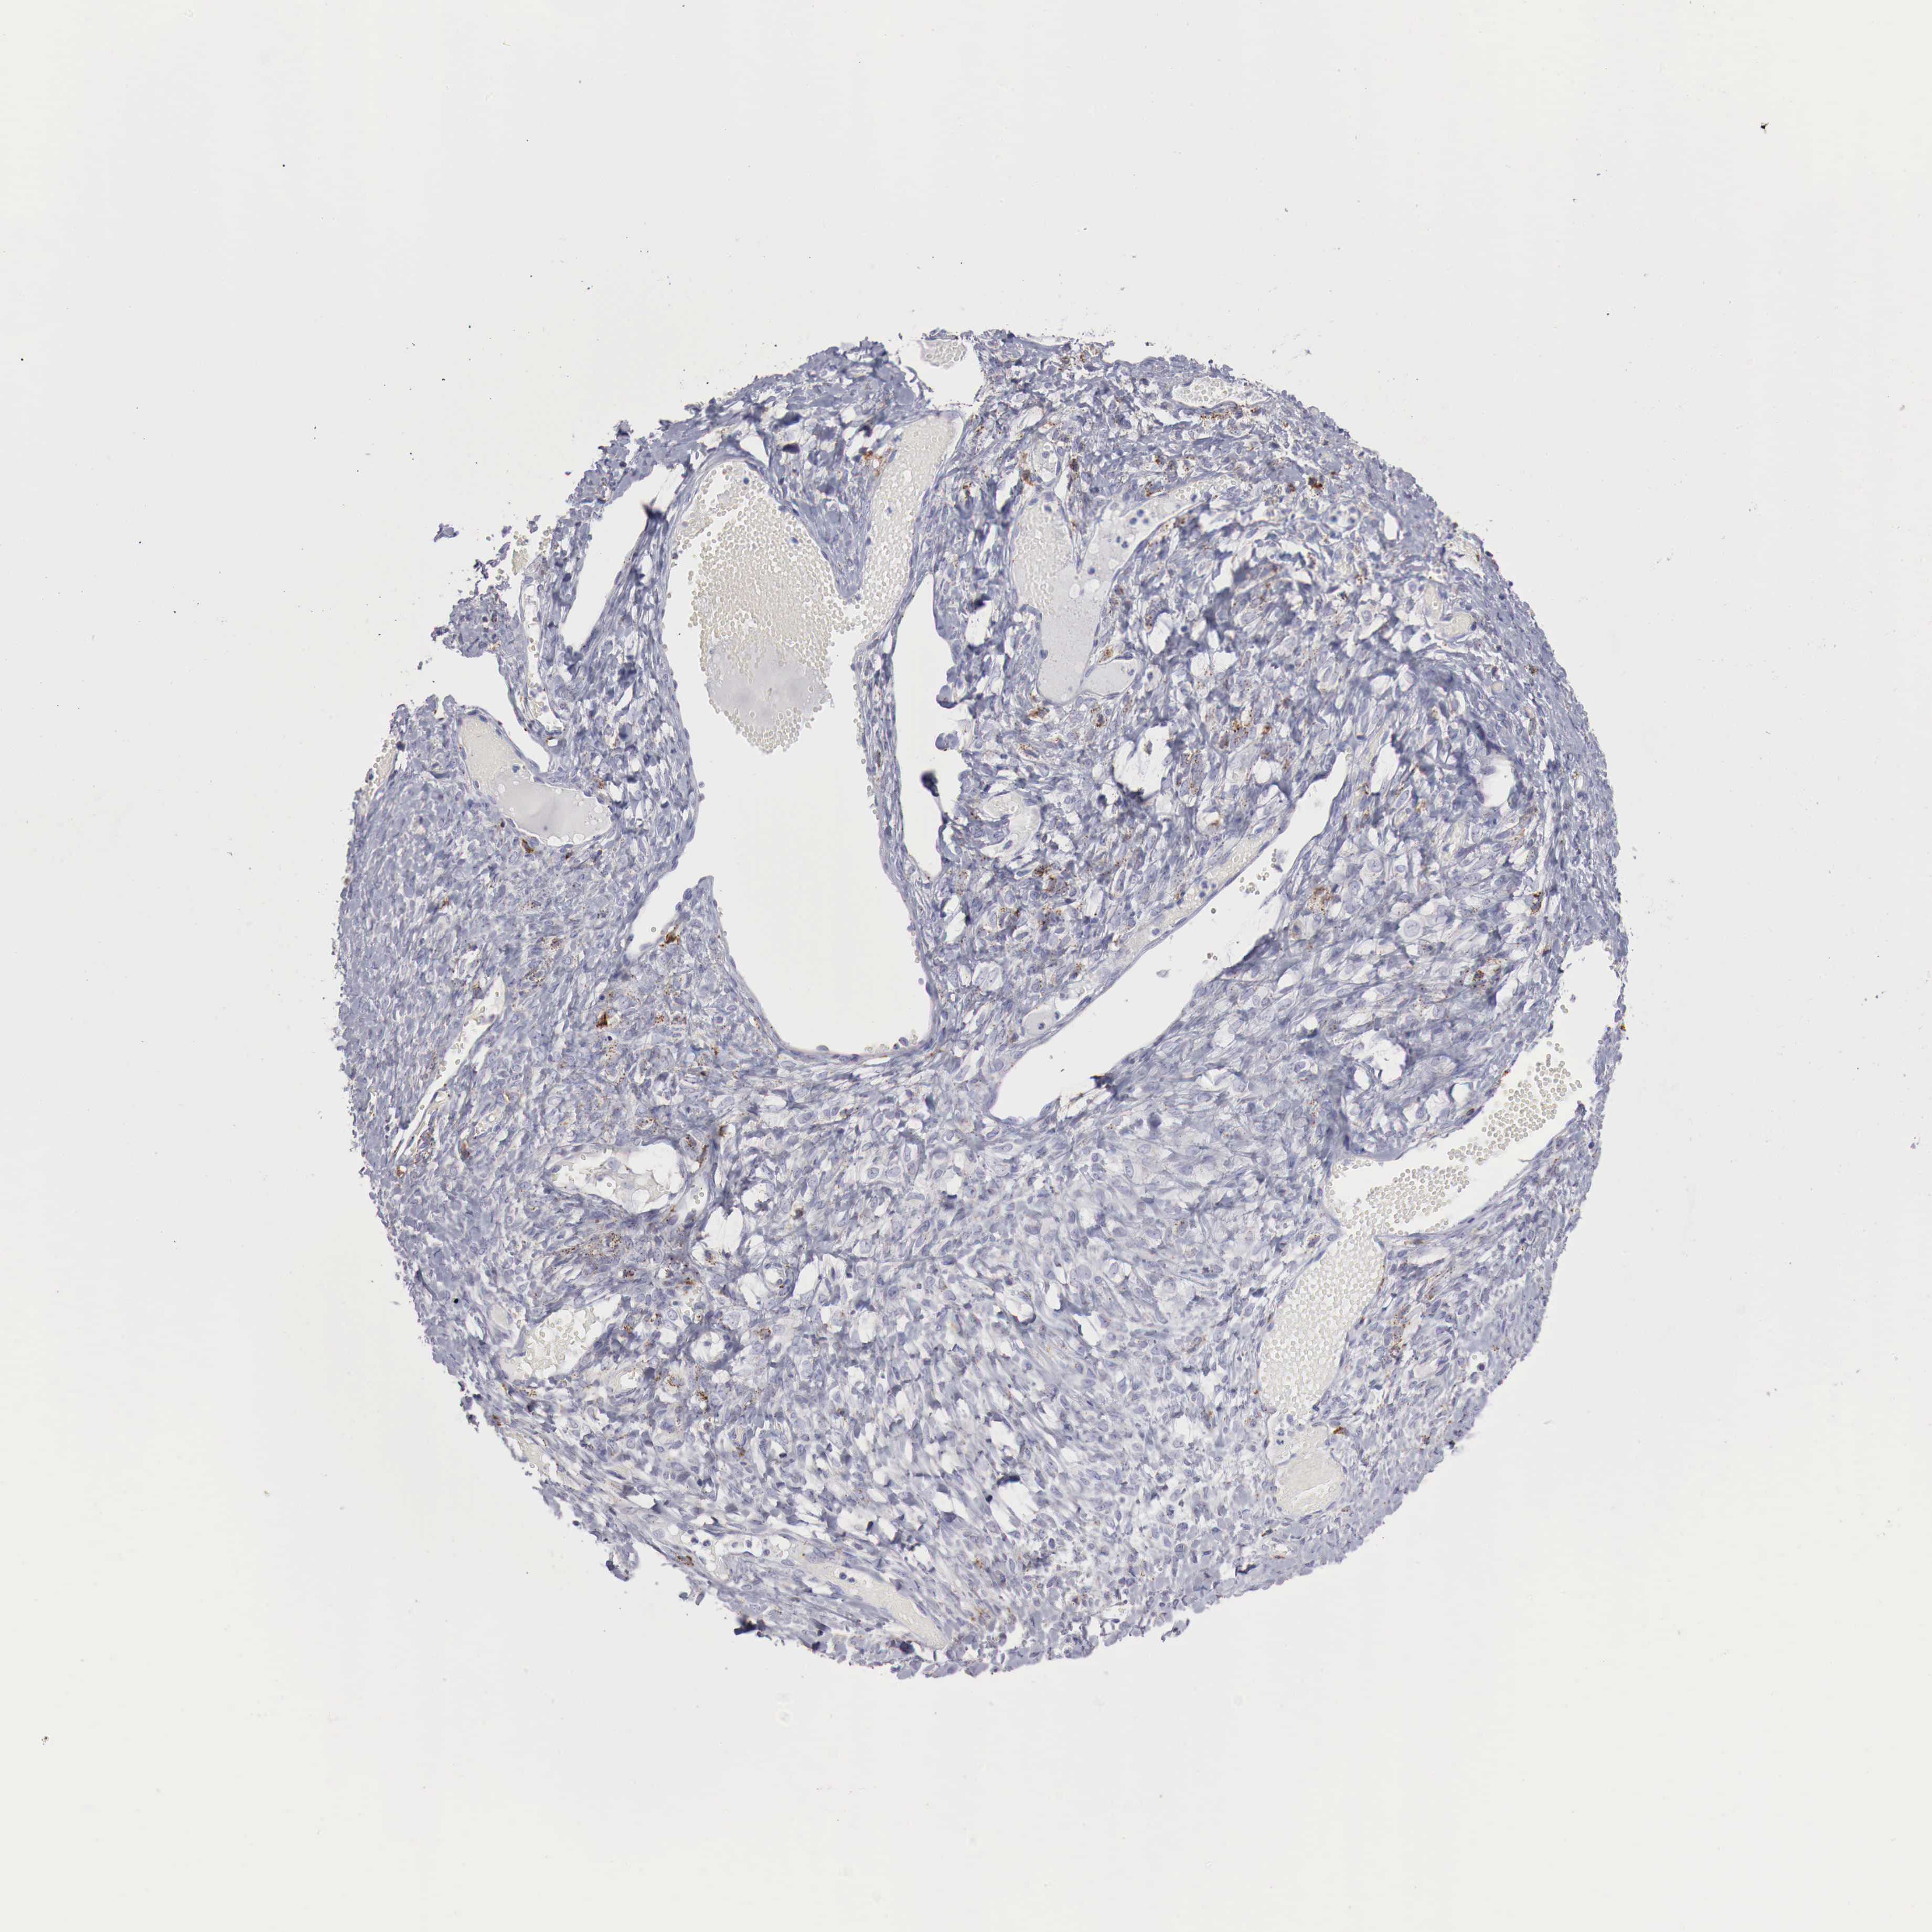

OVARIAN CANCER - Protein expressioni

A mouse-over function shows sample information and annotation data. Click on an image to view it in a full screen mode. Samples can be filtered based on level of antibody staining by selecting one or several of the following categories: high, medium, low and not detected. The assay and annotation is described here.

Note that samples used for immunohistochemistry by the Human Protein Atlas do not correspond to samples in the TCGA dataset.

Antibody stainingi

Antibody staining in the annotated cell types in the current human tissue is reported as not detected, low, medium, or high, based on conventional immunohistochemistry profiling in selected tissues. This score is based on the combination of the staining intensity and fraction of stained cells.

Each image is clickable and will lead to virtual microscopy that enables deeper exploration of all samples and also displays staining intensity scores, fraction scores and subcellular localization as well as patient and tissue information for each sample.

Antibody HPA000237

Antibody HPA000966

Cystadenocarcinoma, mucinous, NOS

Carcinoma, endometroid

Cystadenocarcinoma, serous, NOS